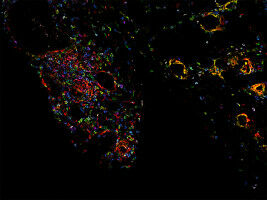

Changes to tumor cells during metastasis depend on certain molecules on the cell surface. Here, the importance of -glycolipids- in the spread of ovarian cancer has been deciphered by a Basel-led international team. These findings could pave the way for new treatment methods. Ovarian cancer is one of the most lethal cancers among women.